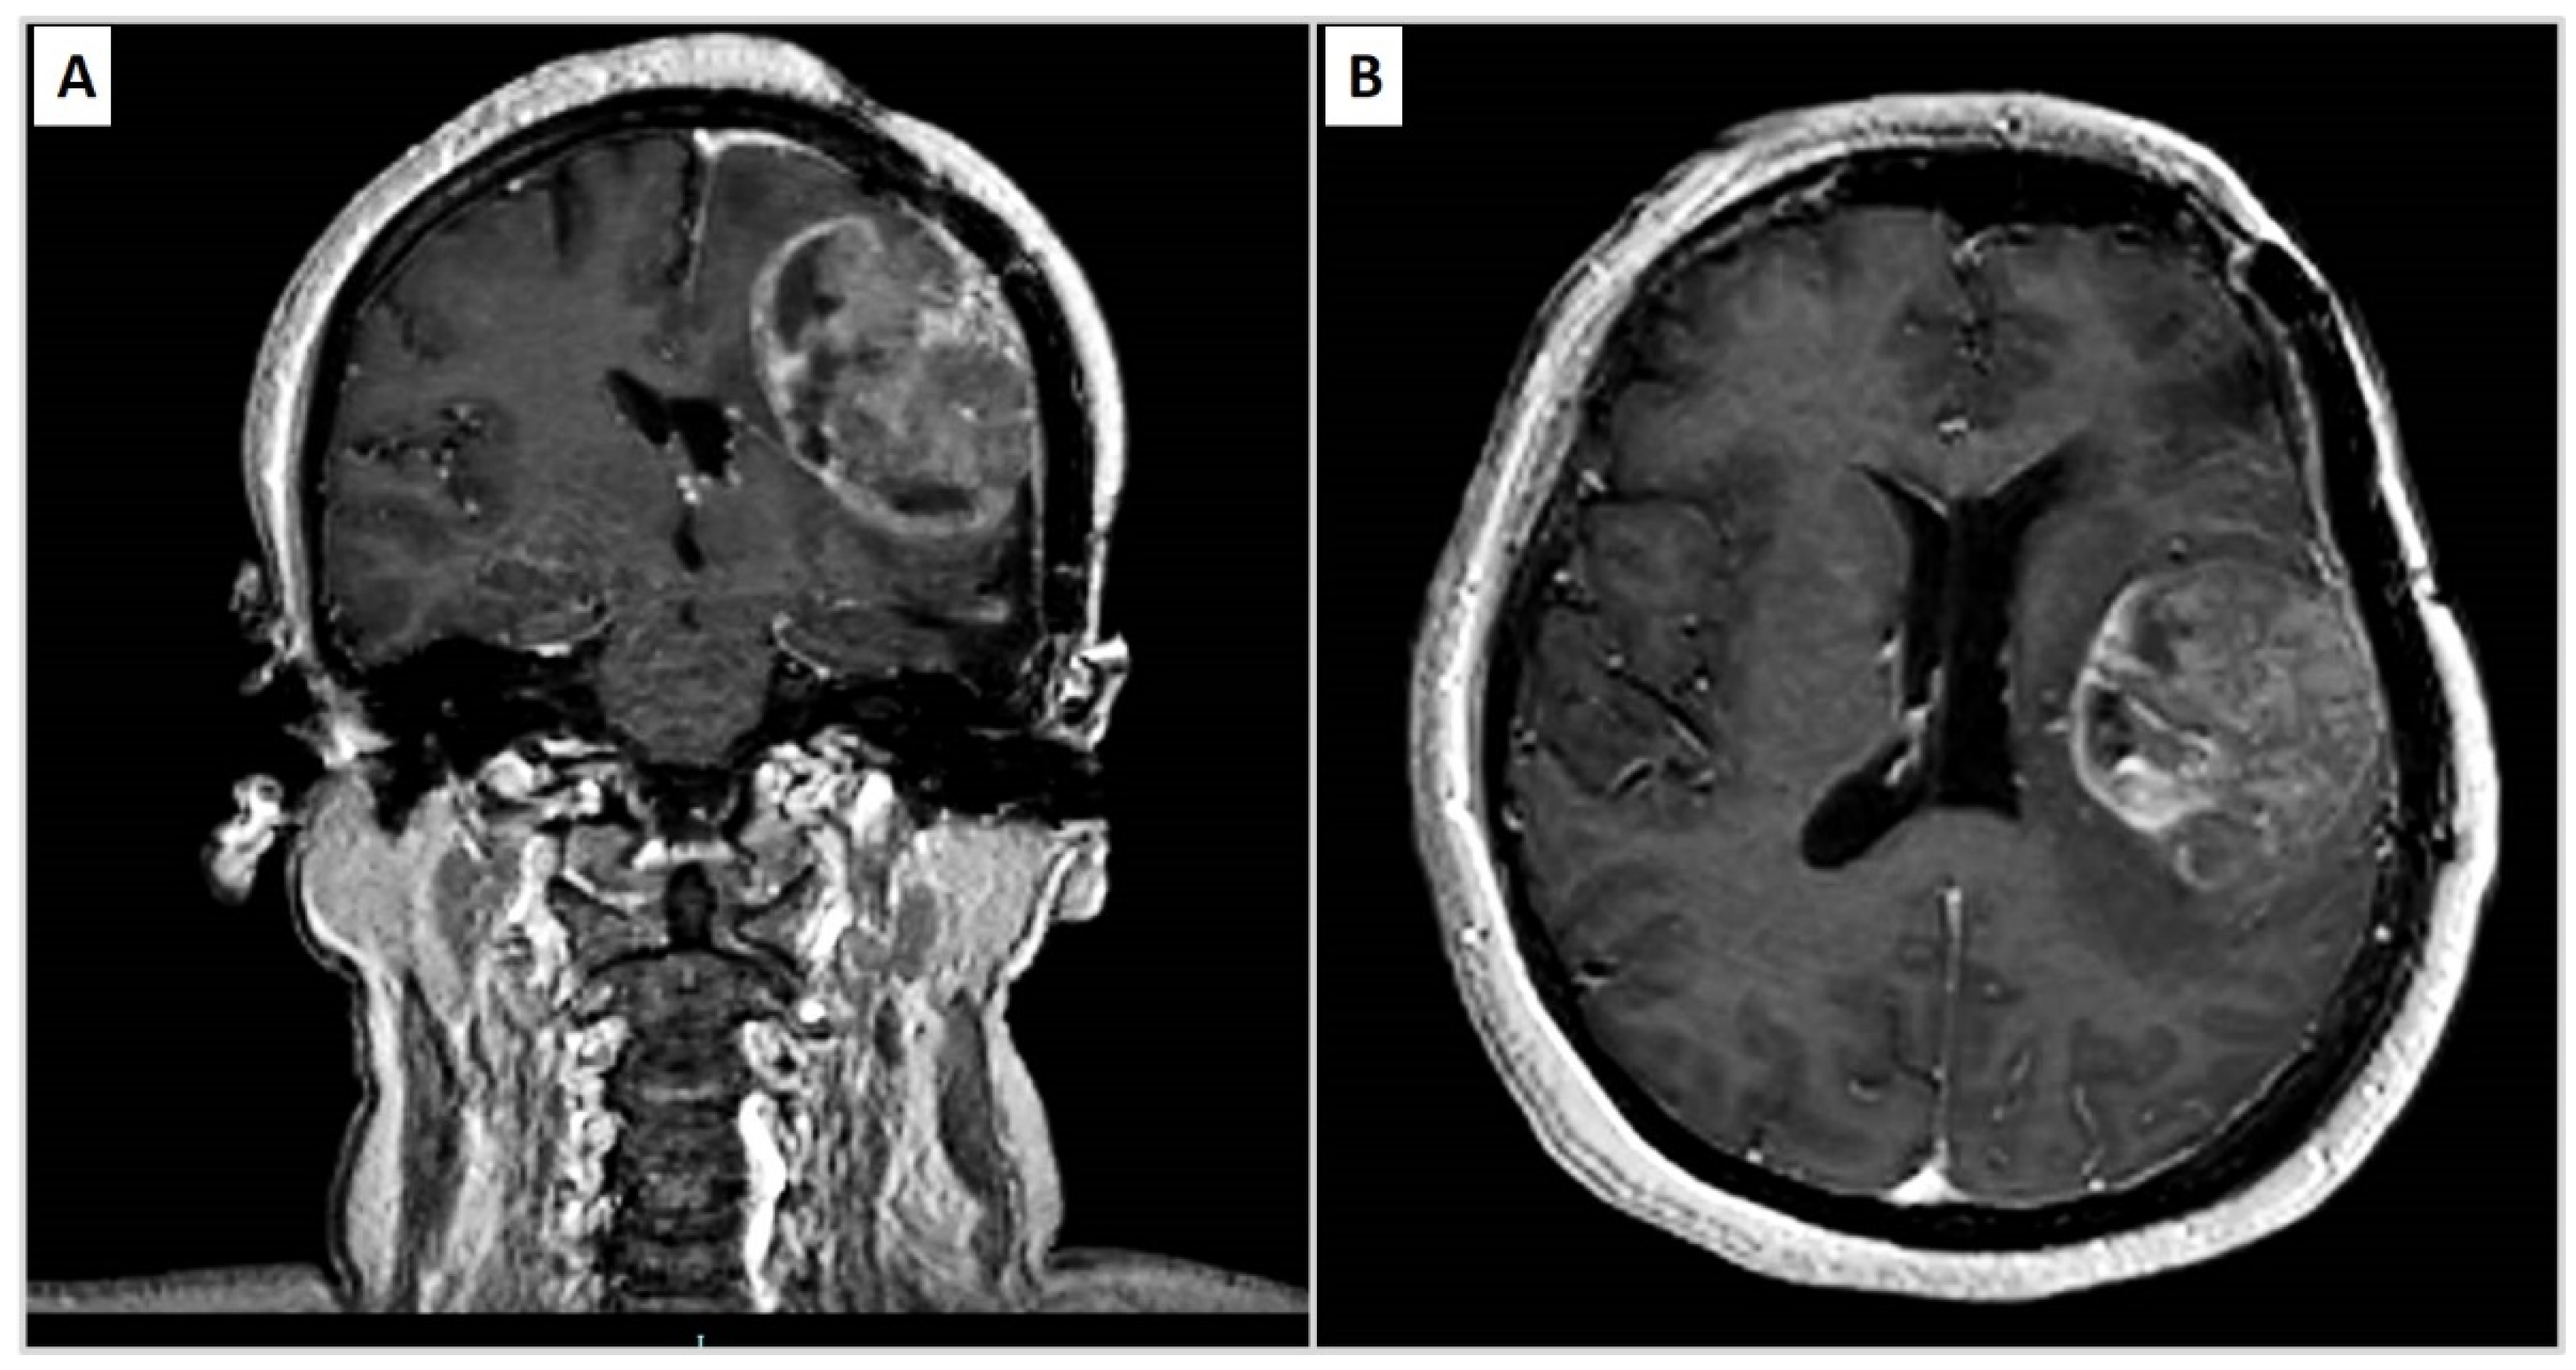

| 2010 | Headache, speech difficulties and hypersomnia | Neoplastic lesion in the left frontparietal area compatible with papillary meningioma | Surgical removal and radiotherapy adjuvant treatment |